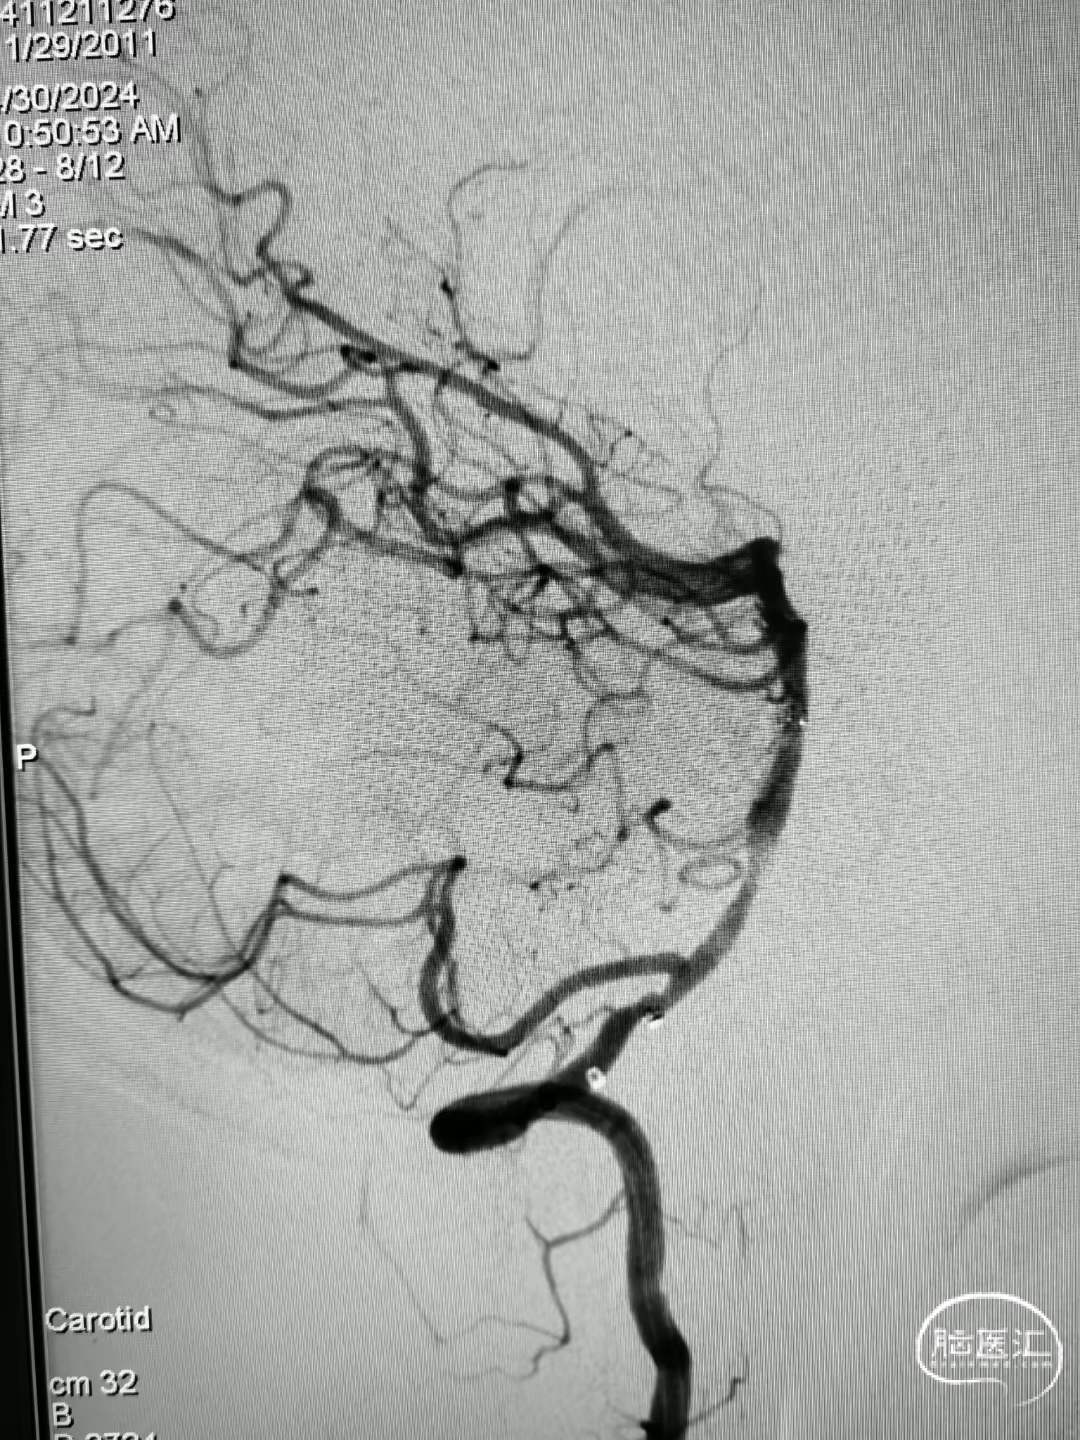

造影见基底动脉闭塞。

a4ca8e833a2e8a51bafe6033253675cc.jpg